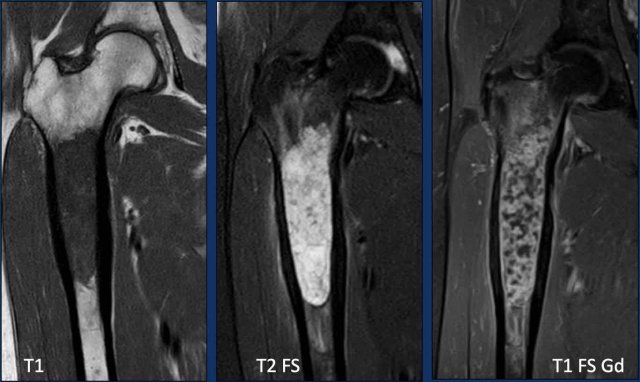

Images

T1W-image shows marrow replacement.

T2W-image shows periosteal reaction

and perilesional bone marrow edema.

The tumor itself is hyperintense and

nodular.

T1W FS post Gd-image shows rings-and-arcs

enhancement pattern.

Conclusion

All these findings are in keeping

with a chondroid tumor, and very suspicious of a chondrosarcoma of grade II or

higher.